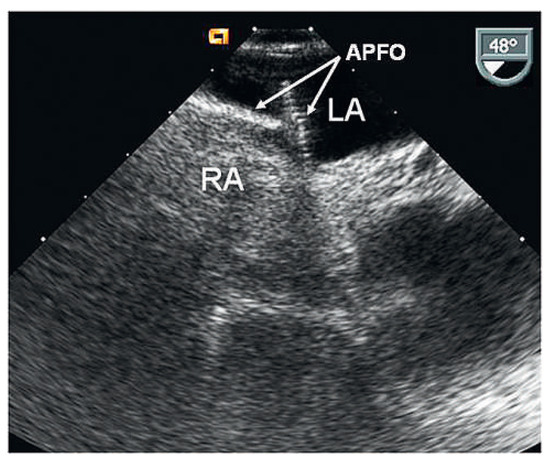

Waiting for Evidence Seems to Make Sense—Except for the One Providing the Evidence

A 58-year-old male presented with a history of two prior transient ischaemic attacks and was found to have a patent foramen ovale (PFO) in the absence of atrial fibrillation or relevant carotid atheromatosis. PFO closure was deferred at this stage due to the [...] Read more.

A 58-year-old male presented with a history of two prior transient ischaemic attacks and was found to have a patent foramen ovale (PFO) in the absence of atrial fibrillation or relevant carotid atheromatosis. PFO closure was deferred at this stage due to the lack of clinical evidence. Three years later the patient was re-admitted after a major stroke with residual symptoms and finally underwent PFO closure in a minimally invasive procedure using an Amplatzer PFO Occluder. Full article